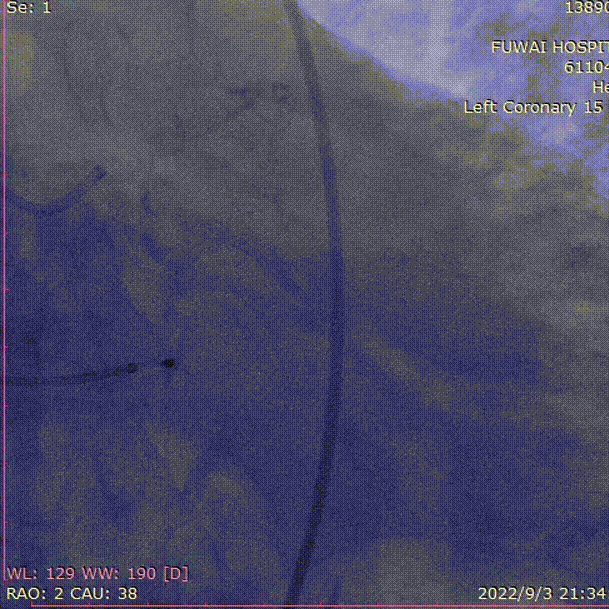

1、冠脉造影和抉择急诊PCI和急诊TAVR

右冠造影